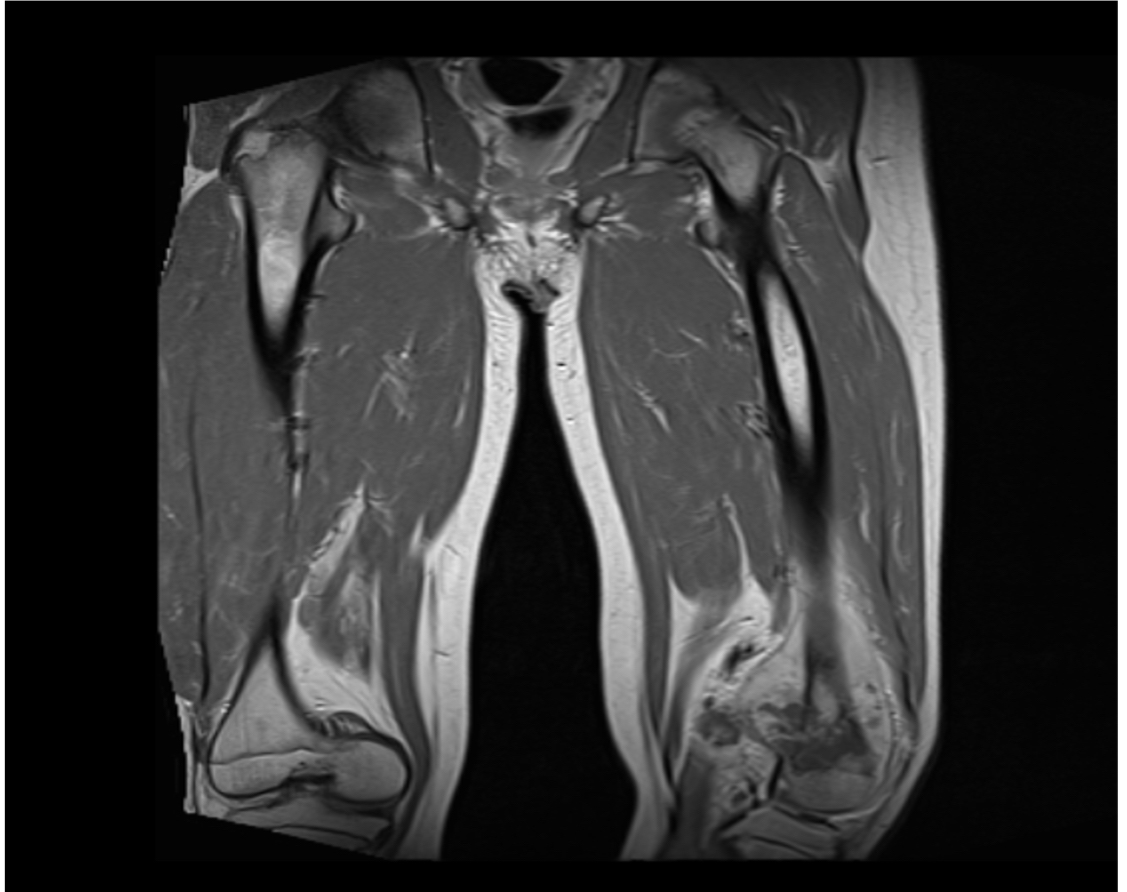

Osteosarcoma multicéntrico sincrónico en paciente pediátrico de 15 años. Reporte de un caso

Gabriel J David Tarud, Luisa Fernanda Atunes Ortega, Katiuska R Molina Pacheco, Tufith A Atunes Celedón

215-221

PDF

HTML

DOI:

https://doi.org/10.14295/rp.v55i4.333